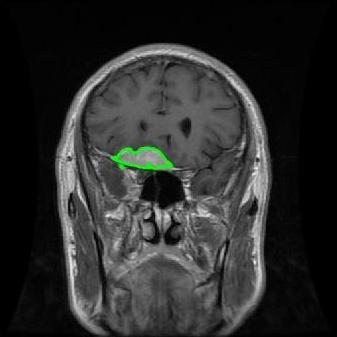

4.3 Comparison with cardic MR images for right ventricle segmentation

Cardiac MRI images often suffer from intensity inhomogeneity due to the varying magnetic susceptibility of cardiac tissues. This can lead to ambiguous boundaries, making it hard for models to consistently identify the left ventricle. Moreover, the heart is composed of several complex anatomical structures, including chambers, valves, and surrounding tissues. Accurately delineating the borders between these various components can be difficult, especially when they are closely positioned or exhibit similar intensity characteristics. In this section, we demonstrate the effectiveness of the RefLSM in segmenting cardiac MR images. The cardiac MR images are standardized to a size of . To enhance the credibility of the proposed model, we segmented 5 cardiac MR images compared the results with 6 other models, including the ALF [MA2019201], LoGRSF [DING2017224], ABC [WENG2021115633], RESLS[8765635], ICTM [WANG2022108794] and FeaACM [XUE2024110673] models. Fig. 5 displays the partial results from all the segmentation models. It is clear that the segmentation results from the RefLSM closely align with the ground truth of the left ventricle segmentation. However, the ALF model demonstrates relatively poor ability to capture the overall structure of the left ventricle; it exhibits limitations with precise boundary detection, particularly in areas of intensity inhomogeneity. Consequently, the evolution curve of the ALF fits into an unstable wave-like result. Suffering from intensity inhomogeneity and surrounding anatomical structures, the LoGRSF model, ABC model and RESLS model all represent over-segmentation and under-segmentation to some extent. Additionally, the results in the 6th column of Fig. 5 show multiple instances where where the ICTM model inaccurately identifies adjacent myocardial tissues as part of the left ventricle due to their similar intensity, leading to false positives. While the FeaACM demonstrates some ability to segment the left ventricle, it is not robust and fails to segment the 5th row of Fig. 5. The 2nd and 3rd rows also include small adjacent excessive regions. In contrast, our proposed model demonstrates marked improvements in accurately capturing the left ventricle’s boundaries. It effectively addresses challenges associated with severe intensity inhomogeneity and noise, resulting in better segmentations. The proposed method appear to maintain better structural integrity in the segmented images, closely aligning with the ground truth.

To quantitatively measure the segmentation results of each model, we compute the Dice and Precision values for left ventricle segmentation. Moreover, we opted for a voilin plot to effectively compare the RefLSM with six other models, as shown in Fig. 7. The results clearly demonstrate that the RefLSM yields superior Dice and Precision values than the other representative models, indicating its closer alignment with the ground truth and highest segmentation accuracy.